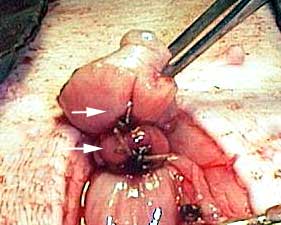

The blood supply to the ovary is extensive, so a special technique is utilized to prevent hemorrhage. This technique involves the use of special clamps. The smaller arrow on the top points to the ovary, which will be removed along with the clamp. The 2 larger arrows on the bottom point to two sutures used to tie off (called ligation) the blood supply to the ovary.

This area is called the pedicle, and will be replaced back into the abdomen when the surgery is complete.